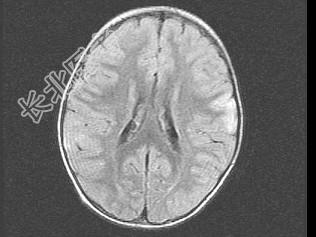

- 单项选择题女,3岁, 头痛、呕吐1周,结合MRI图像, 最可能的诊断是 ( )

A、脑膜炎

B、硬膜下出血

C、脑转移瘤

D、脑梗死

E、脑脓肿